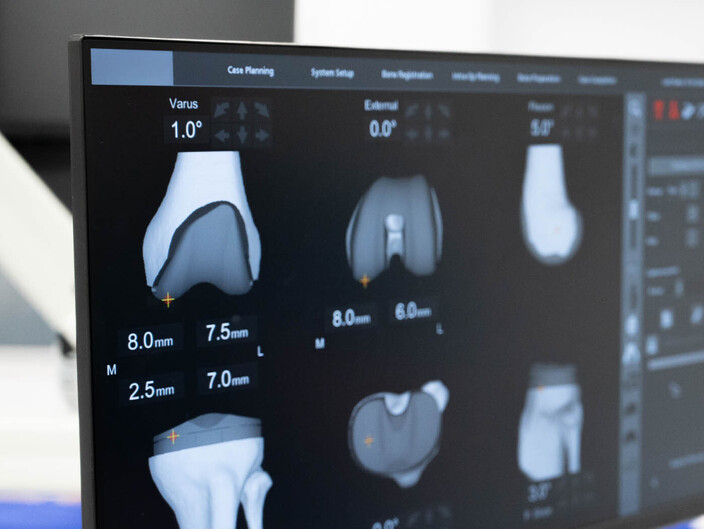

Plain film x-rays are taken to assess the joint

These are usually taken prior to your appointment. These help to confirm the diagnosis, assess the wear pattern and look for particular deformities. They can show old metalware and its position in the bone.